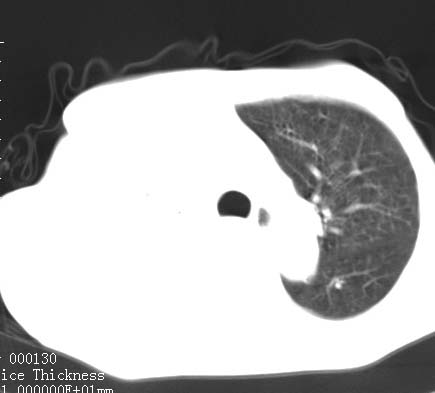

病人女 60岁 咳嗽 气促十余天,大叶性肺炎.

右肺上下叶均见 大片状密度增高影,边界清晰,其内可见支气管充气征,气管支气管通畅。纵膈略向右移位,其内无肿大淋巴结影。首先考虑炎性病变。不排除一些特异性的炎症。不知道发烧吗??wbc高吗??建议治疗后复查!!

看影响还是首先考虑炎性改变,建议实验室检查,还有要警惕炎性肺泡癌,具有的枯枝征象。

看影像还是首先考虑炎性改变,建议实验室检查,还有要警惕炎性肺泡癌,具有的枯枝征象